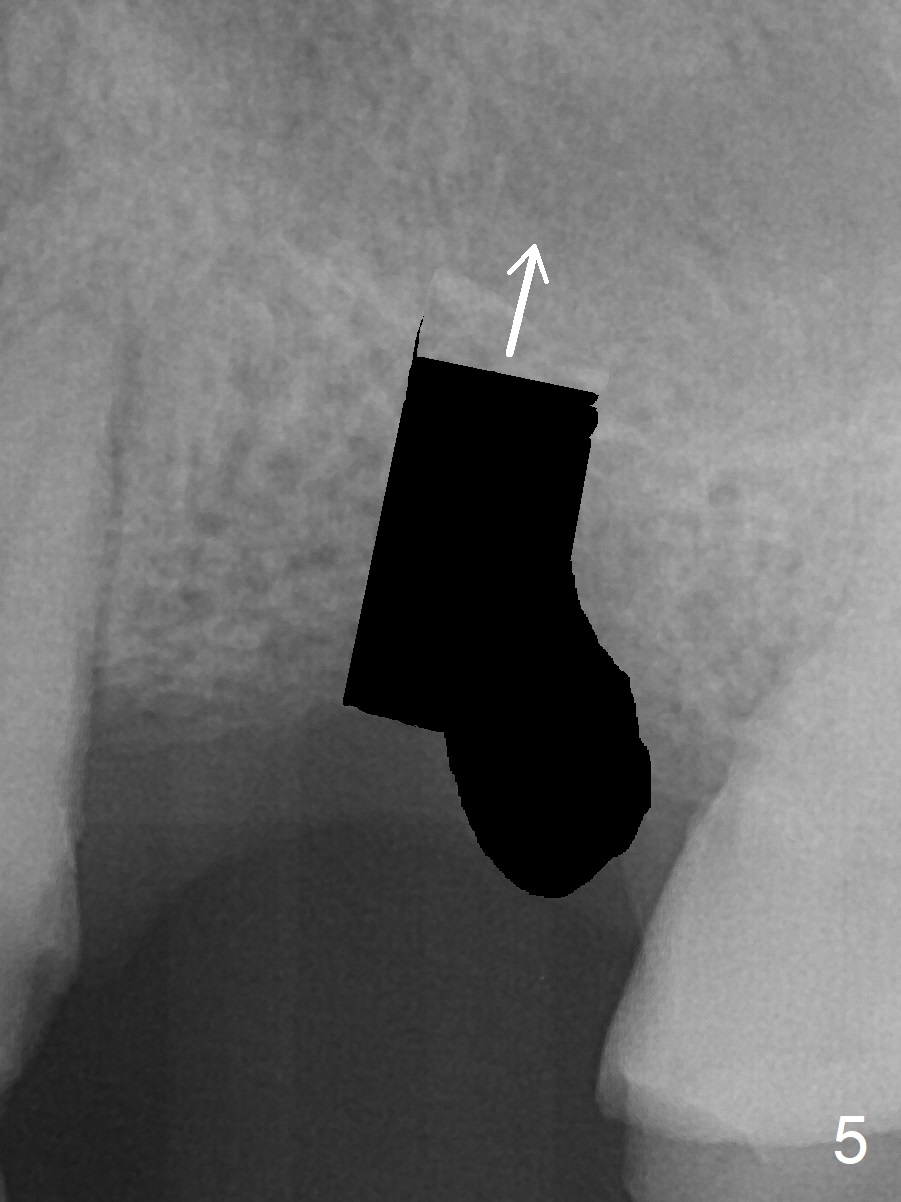

A 37-year-old man will return for #14 extraction and implant after RCT at #13 (Fig.1). After extraction (Fig.2), use Magic Expander (ME) along the long axis of the socket to initiate osteotomy shy of the sinus floor (Fig.3 (<9 mm gingival level)) and change the trajectory at the same time (Fig.4 white arrow). Take the 1st intraop PA when a small ME is stable. Gradually increase the depth for sinus lift as the diameter of MEs increases (Fig.5). Take preop photos to show the residual root and the alveolus (whether it is atrophic or not). Place bone graft (Fig.6 red circles) prior to dummy implant (green).